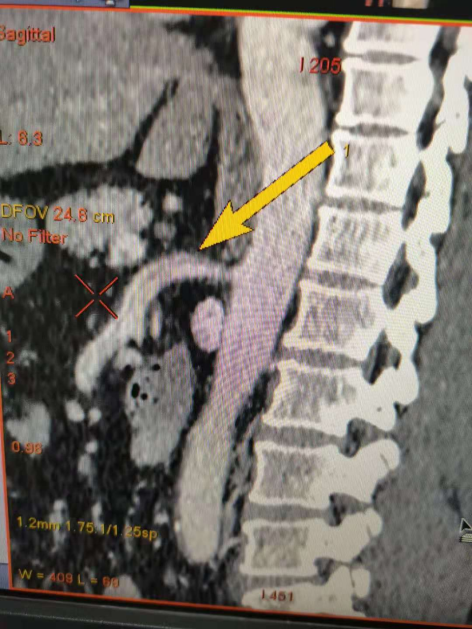

放射科醫(yī)生再次仔細(xì)查看所有血管,發(fā)現(xiàn)腸系膜上動(dòng)脈有一點(diǎn)增粗,管徑約1cm(正常值是0.6—0.9cm),血管壁周?chē)居幸恍┠:S即建議患者做個(gè)全主動(dòng)脈CTA,結(jié)果顯示是腸系膜上動(dòng)脈夾層,立即轉(zhuǎn)入總院急診介入手術(shù),術(shù)后患者體征平穩(wěn)。

圖表 3 CTA矢狀位平面圖